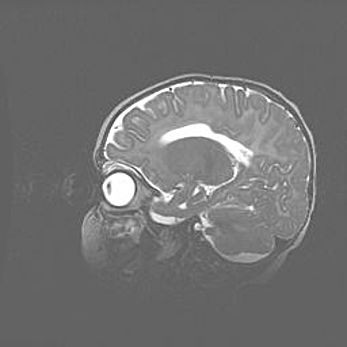

Аномалия Денди-Уокера. Признаки гипоплазии мозолистого тела.

Возраст: 5 месяцев 3 дня

Вес: 5550 г

Пол: мужской

Окружность головы: 39 см

Срок гестации: 40 недель

Аномалия Денди-Уокера – это порок развития головного мозга, для которого характерна триада симптомов: гипотрофия или аплазия червя мозжечка и/или полушарий мозжечка, расширение четвёртого желудочка с формированием ликворной кисты задней черепной ямки, гипертензионная гидроцефалия различной степени.

Гипоплазия мозолистого тела относится к дефектам внутриутробного этапа развития мозговой ткани, возникающим в процессе закладки структур головного мозга, что происходит на начальных этапах развития эмбриона.